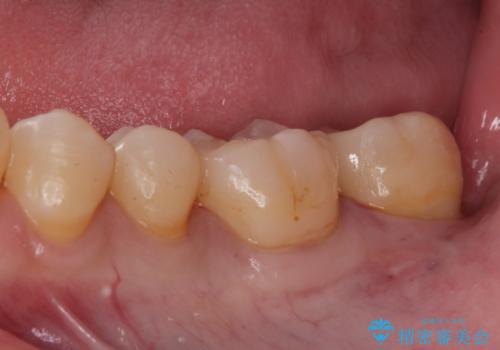

e-maxインレーによる治療

拡大鏡下でう蝕を全て除去してe-maxインレーにて治療を行いました。

e-maxインレーは二次的にう蝕になるリスクが

銀の詰め物や樹脂の詰め物に比べて低いです。